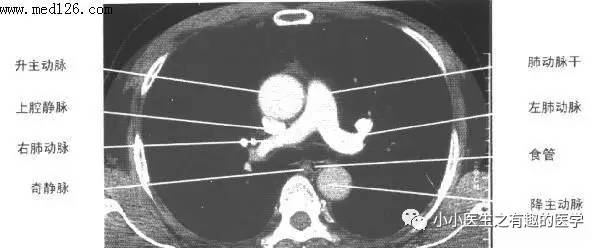

诊断肺栓塞(一般指肺动脉血栓形成),目前临床上基本靠肺动脉CT血管成像,简称肺动脉CTA(A:血管成像angiography),更简单的叫做CTPA(P代表肺:pulmonary)。刚开始看肺栓塞增强CT,觉得很神奇,学会以后才发现,就是那么一点小绝招。

看看下图,这才是正常的肺动脉。

再复习一下,肺动脉乃人字形。